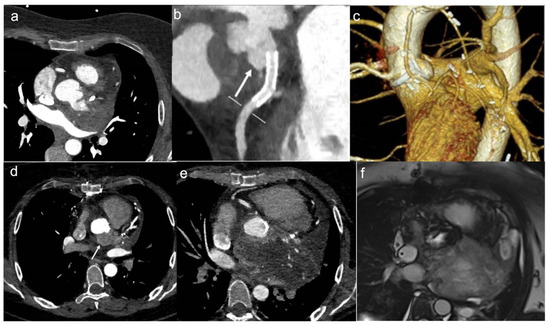

6. Diagnostic Imaging